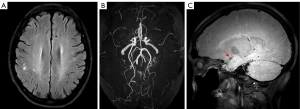

At the time of admission for query stroke in 2004, the patient’s initial brain magnetic resonance imaging (MRI) showed only a few small foci of white matter microangiopathic changes (Figure 1A), with no acute infarction on diffusion-weighted imaging (DWI) (Figure 1B). However, incidental time of flight-magnetic resonance angiography (TOF-MRA) findings of her brain demonstrated occlusion of the bilateral middle cerebral arteries (MCAs) and stenosis of the distal ICAs, with normal anterior cerebral arteries (ACAs) and posterior cerebral arteries (PCAs) (Figure 1C). She was diagnosed with severe intracranial atherosclerosis disease, which was managed conservatively with atorvastatin and aspirin. In the following years, the patient underwent regular imaging surveillance to monitor disease progression. Her recurrent TIAs raised concern, and clinicians considered whether it was feasible for her to receive more aggressive surgery or interventional therapy. In recent years, the condition of her vessels has been reevaluated by multi-sequence MRI, as she is allergic to iodine. The steno-occlusive severity of the patient’s intracranial arteries was assessed by MRA stages for MMD (7). The MRA stages were mainly determined by TOF-MRA maximum intensity projection (MIP) images, with source images used referentially. On the MRA, the steno-occlusive changes of the MCAs, ACAs and PCAs were graded as 3 stages (7): stage 1= no or mild stenosis (<50%), stage 2= moderate stenosis (>50%) but with intact distal segment, and stage 3= severe stenosis without any apparent distal segment. The patient’s moyamoya-type vasculopathy could be classified as stage 3. Surprisingly, the “ivy sign” was not very prominent on fluid-attenuated inversion recovery (FLAIR) images (Figure 2A). It is well known that the “ivy sign” is the result of the slow-flowing leptomeningeal collaterals that can be detected in MMD (8). Although the characteristic “puff of smoke-like” moyamoya vessels were not apparent, her bilateral PCAs were very thick and several branches could be seen originating from the bilateral PCAs and vertebrobasilar arteries (Figure 2B), which could be interpreted as evidence of the development of collaterals from the posterior circulation. High-resolution vessel wall imaging confirmed the intimal thickening and luminal occlusion of MCAs (Figure 2C). The patient’s overall imaging findings were not typical for MMD. With consideration to her medical history, the patient was eventually diagnosed with MMS by a multidisciplinary team (MDT) composed of neurologists, neurosurgeons and diagnostic and interventional radiologists.